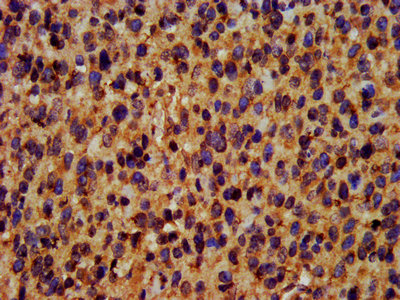

IHC image of CSB-PA892166LA01HU diluted at 1:400 and staining in paraffin-embedded human glioma performed on a Leica BondTM system. After dewaxing and hydration, antigen retrieval was mediated by high pressure in a citrate buffer (pH 6.0). Section was blocked with 10% normal goat serum 30min at RT. Then primary antibody (1% BSA) was incubated at 4°C overnight. The primary is detected by a biotinylated secondary antibody and visualized using an HRP conjugated SP system.